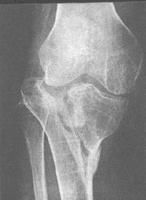

脛骨上端與股骨下端形成膝關節。與股骨下端接觸的面為脛骨平台,也兩個微凹面,並有內側或外側半月板增強凹面,與股骨髁的相對面形成運動軌跡,並增加膝關節的穩定性,脛骨平台是膝的重要負荷結構,一旦發生骨折,使內、外平台受力不均,將產生骨關節炎改變,由於脛骨平台內側分別有內、外側副韌帶,平台中央有脛骨粗隆其上有交叉韌帶附著,當脛骨平台骨折時,常發生韌帶及半月板的損傷。

脛骨平台骨折可由間接暴力或直接暴力引起。高處墜落傷時,足先著地,再向側方倒下,力的傳導由足沿脛骨向上,墜落的加速度使體重的力向下傳導,共同作用於膝部,由於側方倒地產生的扭轉力,導致脛骨內側或外側平台塌陷骨折。當暴力直接打擊膝內側或外側時,使膝關節發生外翻或內翻,導致外側或內側平台骨折或韌帶損傷,根據暴力作用的大小,方向不同,脛骨平台骨折可分為以下類型:

1、單純脛骨外髁劈裂骨折。

2、外髁劈裂合併平台塌陷骨折。

3、單純平台中央塌陷骨折。

4、內側平台骨折,可表現為單純脛骨內髁劈裂骨折或內側平台塌陷骨折。

5、脛骨內、外髁骨折。

6、脛骨平台骨折同時有脛骨幹骺端或脛骨幹骨折。